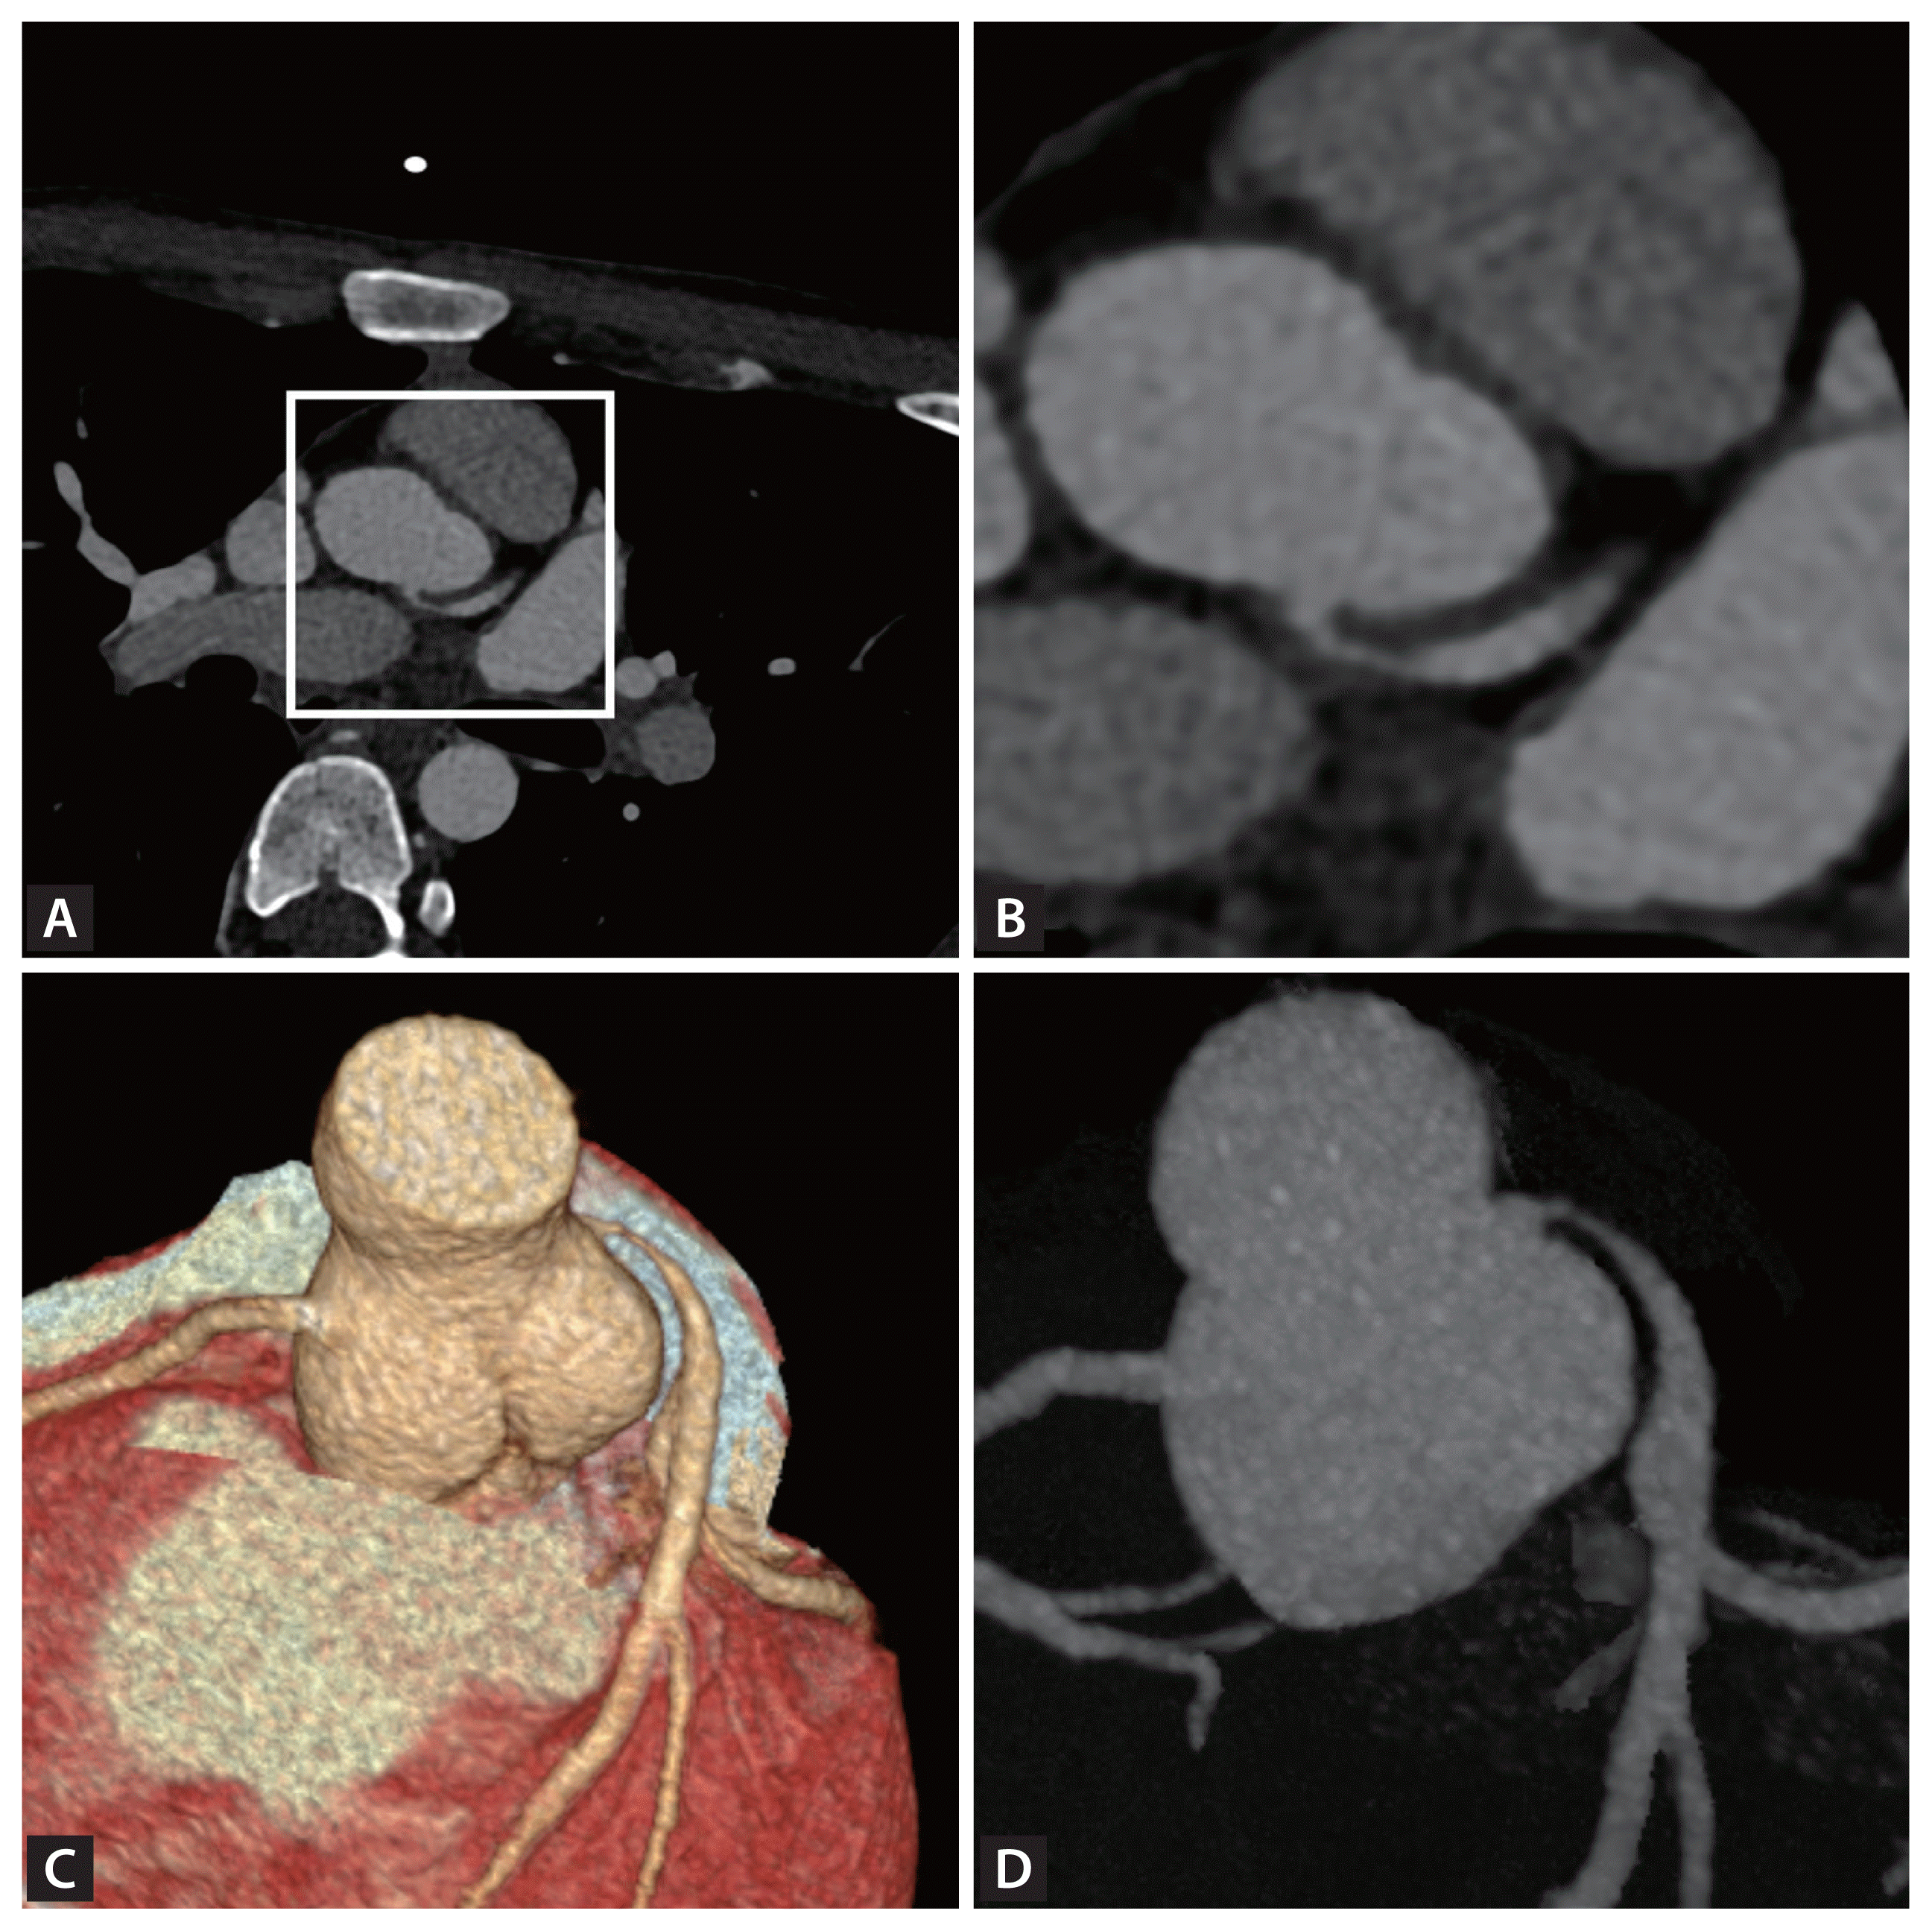

Figure 1

Cardiac computed tomography angiography of the left coronary artery. (A) An axial image of cardiac computed tomography angiography demonstrates severe stenosis at the ostium of the left main coronary artery, which exhibits a high take-off with an acute angle and an interarterial course. (B) Enlarged view of the origin of the left main coronary artery, corresponding to the boxed area in (A). (C, D) Three-dimensional volume-rendered and maximum intensity projection images illustrate a relatively high take-off with an acute angle of the left main coronary artery.

Electrocardiography and echocardiography results were within normal limits. However, cardiac computed tomography angiography revealed significant left main coronary artery (LMCA) stenosis due to an acute angle and relatively high takeoff of the LMCA, coursing between the aorta and pulmonary trunk (Fig. 1, Supplementary Video 1). Subsequent coronary angiography confirmed significant LMCA stenosis, and intravascular ultrasound demonstrated gradual narrowing of the proximal vessel lumen compared to distal reference, suggesting extrinsic compression rather than plaque accumulation. (Fig. 2). Considering the patient’s overall clinical assessment and multimodal imaging findings, he underwent coronary artery bypass graft surgery and recovered uneventfully.